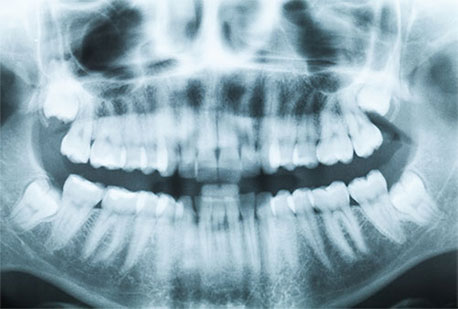

By age 5, digital radiographs are often taken to assess for cavities, and development and/or presence of permanent teeth. There afterwards, radiographs are taken every one and a half to two years if cavities are not present (in cavity prone children we may require radiographs every 6-12months).

Digital Radiographs provide clear full screen dental radiographs in seconds. They produce up to 70% less radiation than traditional films (one full mouth series of up to 18 digital radiographs delivers less radiation than what a person receives in one month from natural environmental sources ie. background exposure). Digital xrays can then be sent via email to other dentists and specialists for additional treatment.